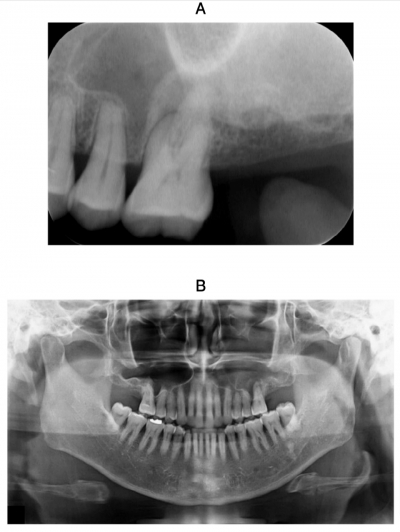

57歳の男性。左側の鼻漏と上顎左側第一大臼歯の咬合時の違和感を主訴として 来院した。1か月前に気付いたが、変化はないという。⎿6は周囲歯肉に発赤と腫脹はみられないが、軽度の打診痛があり、歯髄電気診で生活反応はなかった。初診時のエックス線写真及びCTを示す。

抗菌薬の投与とともにまず行うべき処置はどれか。1つ選べ。